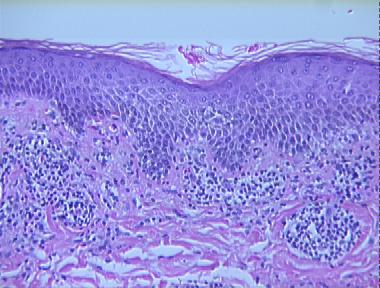

erythema annulare centrifugum

Histologic Features